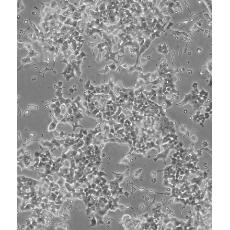

中文名稱 小鼠胰島素瘤胰島β細胞

生長特性 adherent

形態特征 epithelial

細胞描述 這株細胞來源于轉基因小鼠中生長的一個胰腫瘤(胰島素瘤)。這種小鼠攜帶了大鼠胰島素II基因啟動子調控的SV40早期基因的假基因結構。細胞包含豐富的胰島素和小量的胰高血糖素及生長抑素。響應葡萄糖而分泌胰島素